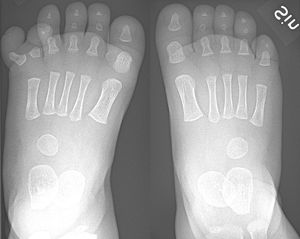

일반적으로 사람은 양 발에 각각 다섯 개의 발가락을 가지고 있으며, 모두 발톱으로 덮여 있다. 발가락 뼈는 지골이라고도 불리며, 뒤꿈치로 뻗어 있는 뼈에 연결되어 있다.

일반적으로 사람의 발에는 다섯 개의 발가락이 있다. 각 발가락은 엄지발가락(halluxla)을 제외하고 근위부, 중간부, 원위부의 세 발가락뼈로 구성된다. 소수의 사람들에게는 새끼발가락에 중간뼈가 없는 경우도 있다. 엄지발가락에는 근위 뼈와 원위 뼈, 두 개의 발가락뼈만 있다. 각 발가락뼈 사이의 관절은 발가락뼈간 관절이다. 각 발가락의 근위 발가락뼈는 중족골과 중족골 발가락 관절에서 관절을 이룬다. 각 발가락은 피부로 둘러싸여 있으며, 다섯 발가락 모두에 발톱이 있다.

사람은 보통 각 발에 다섯 개의 발가락을 가지고 있다. 다섯 개 이상의 발가락이 있는 경우 다지증이라고 한다. 합지증 또는 거미발가락증과 같은 다른 변형도 있을 수 있다. 발가락 모양을 포함한 앞발 모양은 사람마다 상당한 차이를 보인다. 이러한 차이는 측정될 수 있으며 민족과 통계적으로 상관관계가 있다.[3] 이러한 차이는 다양한 신발 유형의 편안함과 착용감에 영향을 미칠 수 있다. 미 육군을 위해 수행된 연구에 따르면 발이 더 큰 경우에도 아치, 발가락 길이, 발가락 너비가 더 작을 수 있다.[4]3. 기능